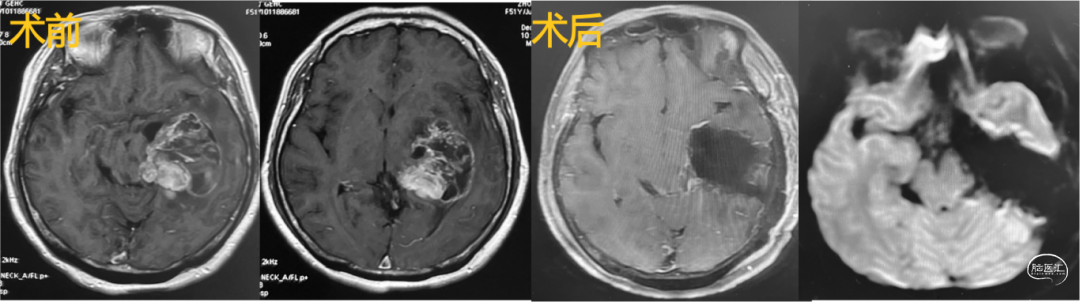

2.小脑-脑干肿瘤切除术